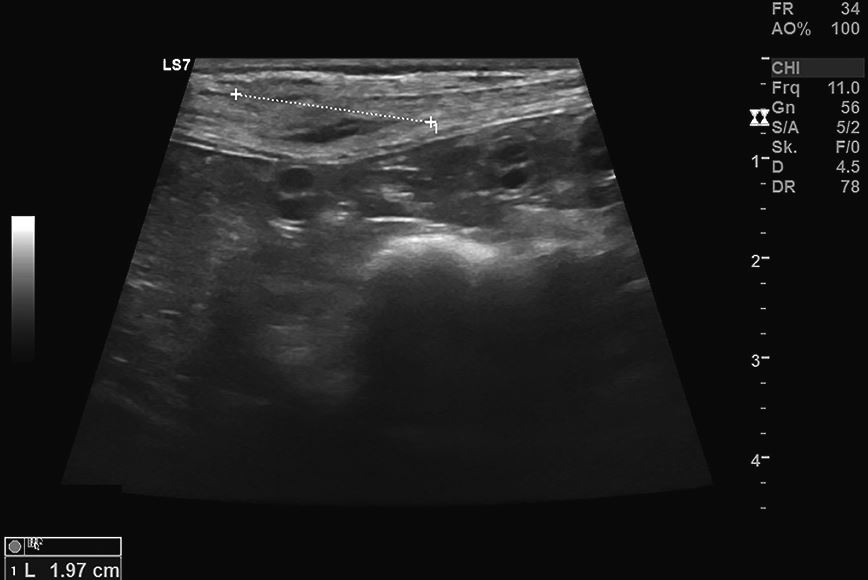

Als weitere diagnostische Maßnahme wurde eine Feinnadelbiopsie der Knoten durchgeführt; sie zeigten eine pyogranulomatöse Entzündung ohne Erregerbeteiligung. Die Sonografie des größten ventralen Hautknotens zeigte eine gut abgegrenzte, ovale und echoarme Umfangsvermehrung der Dermis und des subkutanen Gewebes von circa 2 × 0,6 cm Durchmesser, ohne Infiltration der Bauchdecke und ohne Nekroseanzeichen [Abb. 2].